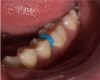

A 28-year-old woman, who previously had braces, had circumferential gumline decalcification (Figure 1) and wished to arrest lesions before they worsened (bitewing, Figure 2). The following protocol is consistent with the product instructions for the resin infiltration material from DMG America, which is the only commercially available resin infiltration system in the US.

Fig 1.  Circumferential gumline decalcification (Fig 1) and bitewing (Fig 2) of a 28-year-old woman.

Figure 1

Fig 2.  Circumferential gumline decalcification (Fig 1) and bitewing (Fig 2) of a 28-year-old woman.

Figure 2